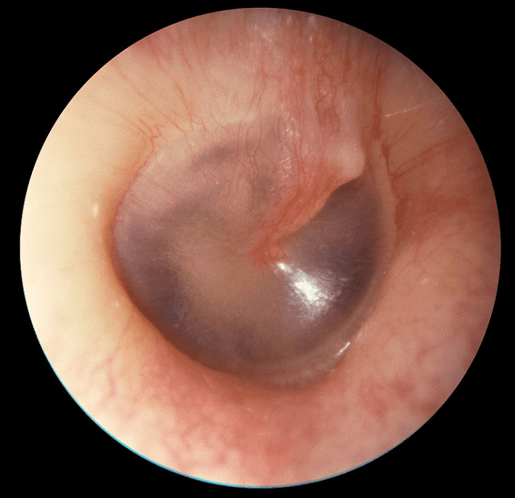

• Normalmente es translúcida, es decir, deja pasar parte de la luz, permitiendo la visualización de las estructuras subyacentes. Cuando está alterado no deja pasar nada de luz y se observa opaco. El tímpano normal tiene una coloración blanco nacarado, a veces, levemente enrojecido o ambarino y con algunos vasos sanguíneos. El llanto o maniobras de Valsalva aumentan esa coloración y también ingurgitan los vasos. Otoscopías con aspecto y coloración alterados

• La forma normal de la membrana timpánica es levemente cónica teniendo como punto más profundo la zona en donde termina el mango del martillo  (umbo o depresión central del tímpano). La posición de la membrana puede ser normal, abombada o retraída.

4. Triángulo luminoso:

• Este triángulo es un brillo de distribución coniforme sobre la membrana timpánica, que se origina a partir de la reflexión de la luz proveniente del otoscopio. Por la posición de la membrana se ubica en el cuadrante anteroinferior. En patología como otitis media aguda en donde la membrana timpánica está engrosada, opaca y abombada el cono luminoso puede desaparecer.